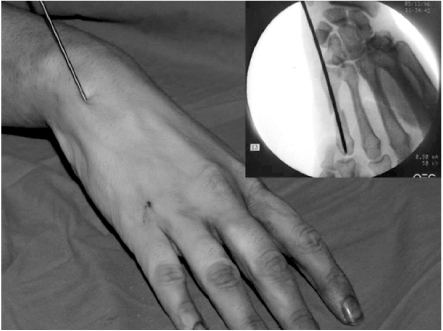

The surgery was performed under general or regional anesthesia with image intensification, preferably with a tourniquet on the upper arm. Under the fluoroscopy, closed reduction of the metacarpal fracture was achieved by manipulation, and 1.6 mm K-wire was inserted from metacarpal head with MP joint flexion for easy access to the medullary canal (Fig. 1). When the wire tip passed fracture site and reach to metacarpal base, wrist was bent maximum and further penetration was performed to proximal area (Fig. 2). The distal end of K-wire was pulled up until its tip end lay within the metacarpal head (Fig. 3). Penetrated proximal part of wire was bent over, cut and buried under the skin (Fig. 4). During this procedure, any rotation of fracture was carefully checked with passive flexion and extension motion of the finger. Ulnar gutter splint was applied for rotational stability and pain relief. It was changed to extension block splint and encouraged motion exercise from postoperatively 1 week. After fracture healing, the wire was removed with local anesthesia in the outpatient department in all cases. We make small skin incision at proximal bended wire and pull out that with local anesthesia.

Fig. 3

The distal end of k-wire is pulled up to metacarpal head.

Fig. 3 The distal end of k-wire is pulled up to metacarpal head.